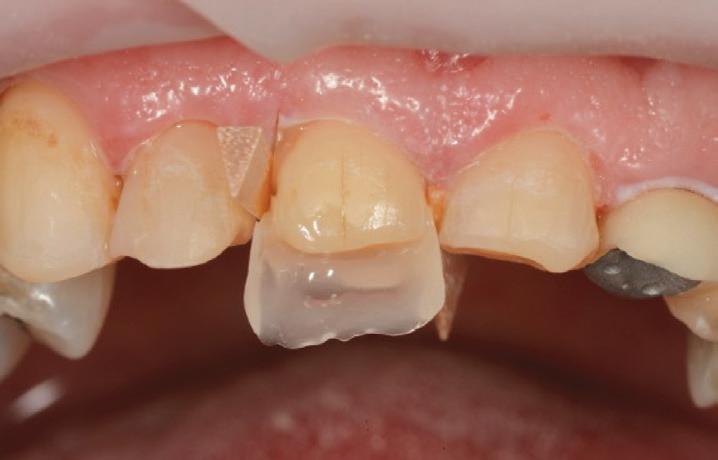

The teeth were cleaned of plaque and the chipped and unsupported enamel was removed (Figs. 4, 5). Fine bevels were placed to facilitate composite adhesion.

Small, 1/2 round bur undercuts were placed, and all of the exposed

dentine (and the old crown) were micro-etched with the Rondoflex 360 sandblaster, using 27um particles (Figs. 6, 7).

The maxillary anteriors were then isolated one at a time, and a selective etch adhesive protocol was used with the adhesive OptiBond™ Universal by KerrTM (Fig. 8).